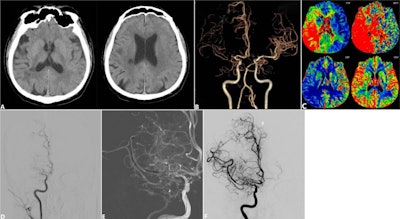

- Adding endovascular recanalization does not improve sNAIAO treatmentby Amerigo Allegretto on January 6, 2026 at 7:08 am

Adding endovascular recanalization does not improve outcomes for symptomatic nonacute intracranial artery occlusion (sNAIAO).